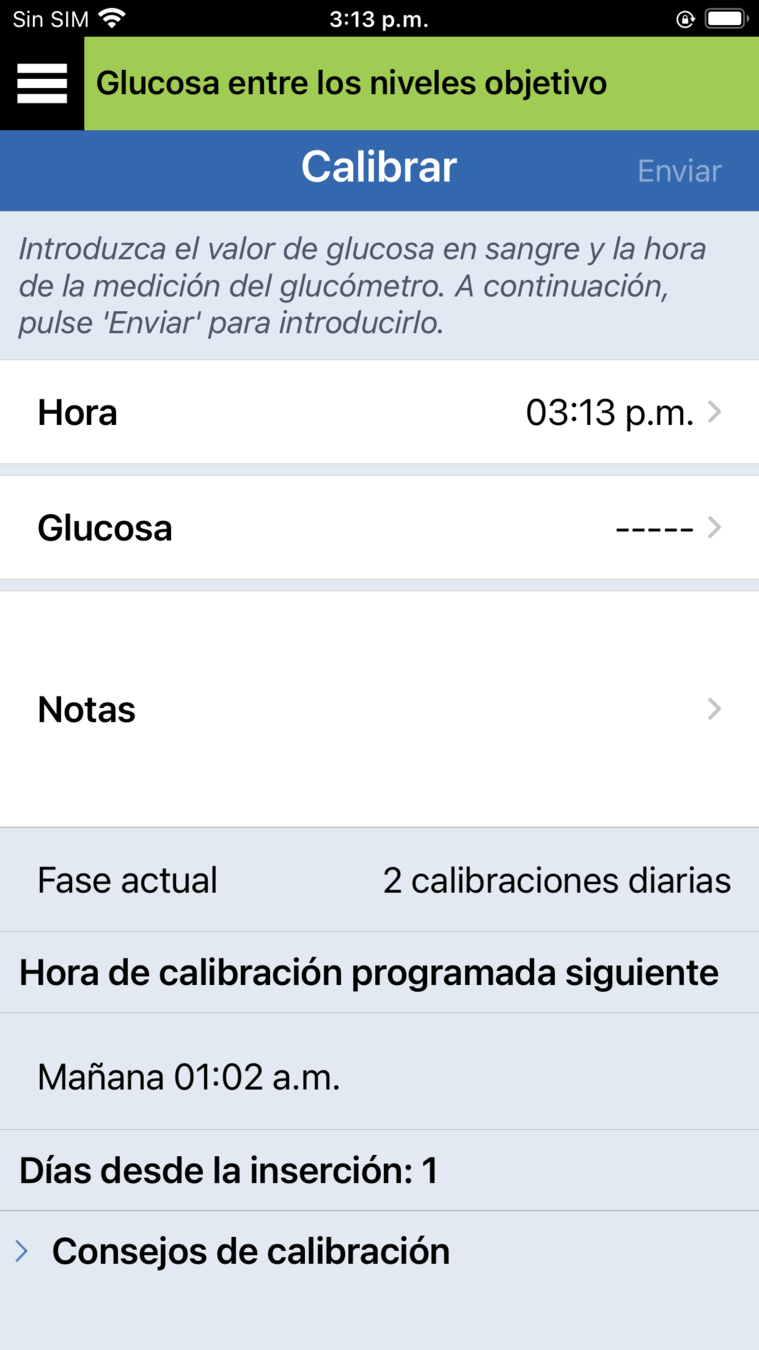

Ahora que ha colocado correctamente el transmisor inteligente Eversense® E3, verá en la aplicación móvil una notificación Calibrar ahora al cabo de unos minutos .

Esto quiere decir que es hora de realizar la primera de las 4 calibraciones mediante punción capilar.

4 CALIBRACIONES DE INICIALIZACIÓN

Para introducir una calibración, haga una comprobación de glucosa en sangre mediante punción capilar…

… y toque en el botón Calibrar.

INTRODUZCA UNA CALIBRACIÓN

INTRODUZCA UNA CALIBRACIÓN

Toque Glucosa…

INTRODUZCA UNA CALIBRACIÓN

… y desplácese para introducir el valor correcto de glucosa en sangre.

A continuación, toque OK.

Toque Glucosa…

INTRODUZCA UNA CALIBRACIÓN

Confirme que se han introducido los valores correctos de glucosa y, a continuación, toque Enviar.

… y desplácese para introducir el valor correcto de glucosa en sangre.

A continuación, toque OK.

Toque Glucosa…

Recibirá una notificación de Calibración en curso, que podrá borrar pulsando Terminado.

Confirme que se han introducido los valores correctos de glucosa y, a continuación, toque Enviar.

… y desplácese para introducir el valor correcto de glucosa en sangre.

A continuación, toque OK.

Toque Glucosa…

PANTALLA CALIBRAR

Si se desplaza a la pantalla Calibrar desde

el menú principal, puede comprobar

lo siguiente:

PANTALLA CALIBRAR

- en qué fase de calibración diaria se encuentra;

Si se desplaza a la pantalla Calibrar desde

el menú principal, puede comprobar

lo siguiente:

- cuándo hay que realizar la próxima calibración.

Pantalla Calibrar

- en qué fase de calibración diaria se encuentra;

Si se desplaza a la pantalla Calibrar desde

el menú principal, puede comprobar

lo siguiente:

Si le resulta más cómodo según su día, tiene la opción de calibrar antes, es decir, antes de recibir la alerta de que hay que efectuar una calibración.

- cuándo hay que realizar la próxima calibración.

- en qué fase de calibración diaria se encuentra;

Si se desplaza a la pantalla Calibrar desde

el menú principal, puede comprobar

lo siguiente:

Una vez que haya realizado las 4 calibraciones de inicialización y que esté recibiendo datos continuos de la glucosa, pasará a la fase de 2 calibraciones diarias.

Durante los siguientes 21 días, tendrá que calibrar 2 veces al día. Una vez finalizada esta fase, tendrá que calibrar al menos una vez al día (pero no más de dos veces al día).